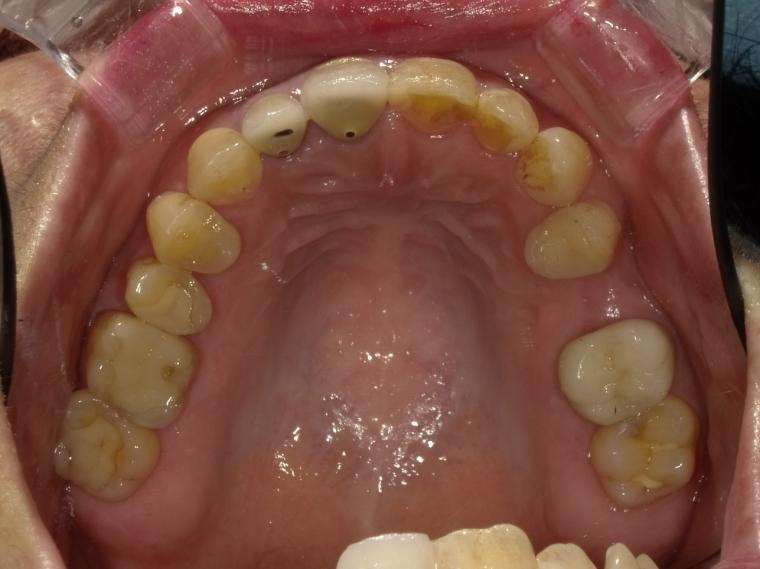

BEFORE

58歳女性/上下2本欠損/インプラント埋込手術

左上第二小臼歯が欠損状態で、インプラントのご相談でご来院された患者さんです。

左下第一大臼歯も、根っこの先で炎症が広がっており、抜歯後に左上と一緒にインプラントを埋入しました。